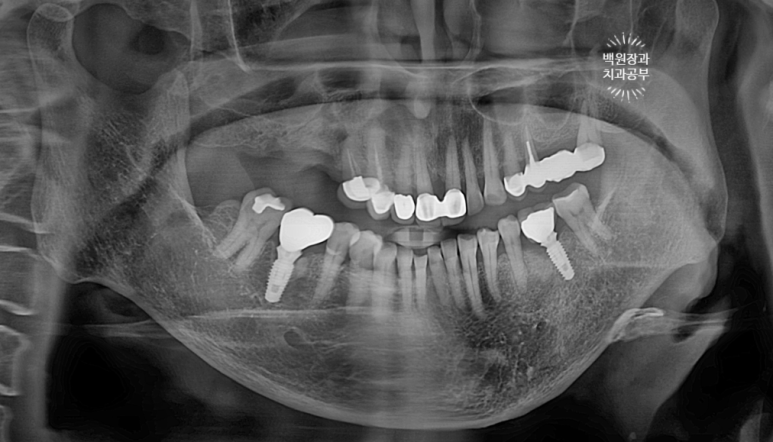

노란 점선이 보이시나요? 잇몸뼈의 높이입니다.

상당한 양의 임플란트 주변 뼈가 녹아서 없어져 버린것을 보실 수 있어요.

수술 후 찍은 치과용 파노라마 엑스레이를 보시면,

임플란트가 사라진 자리에 충분히 자리잡은 뼈이식재를 보실 수 있을거에요!